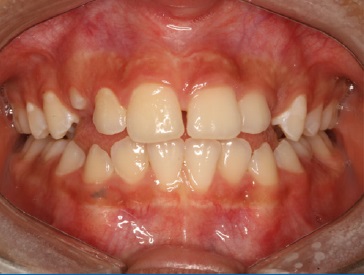

A paciente retornou para acompanhamento clínico após 12 meses (Figura 8), realizada uma nova avaliação funcional, na qual a paciente possuía Classe II de Angle subdivisão esquerda, além de discreta falta de espaço para a erupção do canino esquerdo e foi encaminhada para o ortodontista.